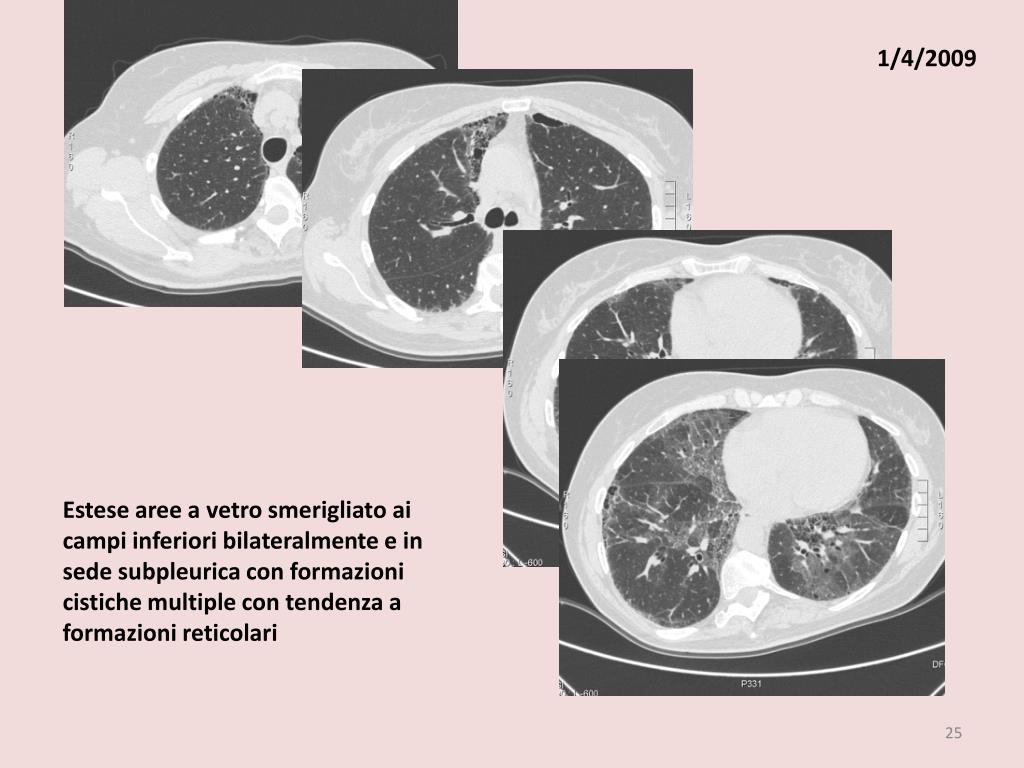

4. 1/4/2009 Estese aree a vetro smerigliato ai campi inferiori bilateralmente e in sede subpleurica con formazioni cistiche multiple con tendenza a formazioni reticolari

19. 1/4/2009 Estese aree a vetro smerigliato ai campi inferiori bilateralmente e in sede subpleurica con formazioni cistiche multiple con tendenza a formazioni reticolari